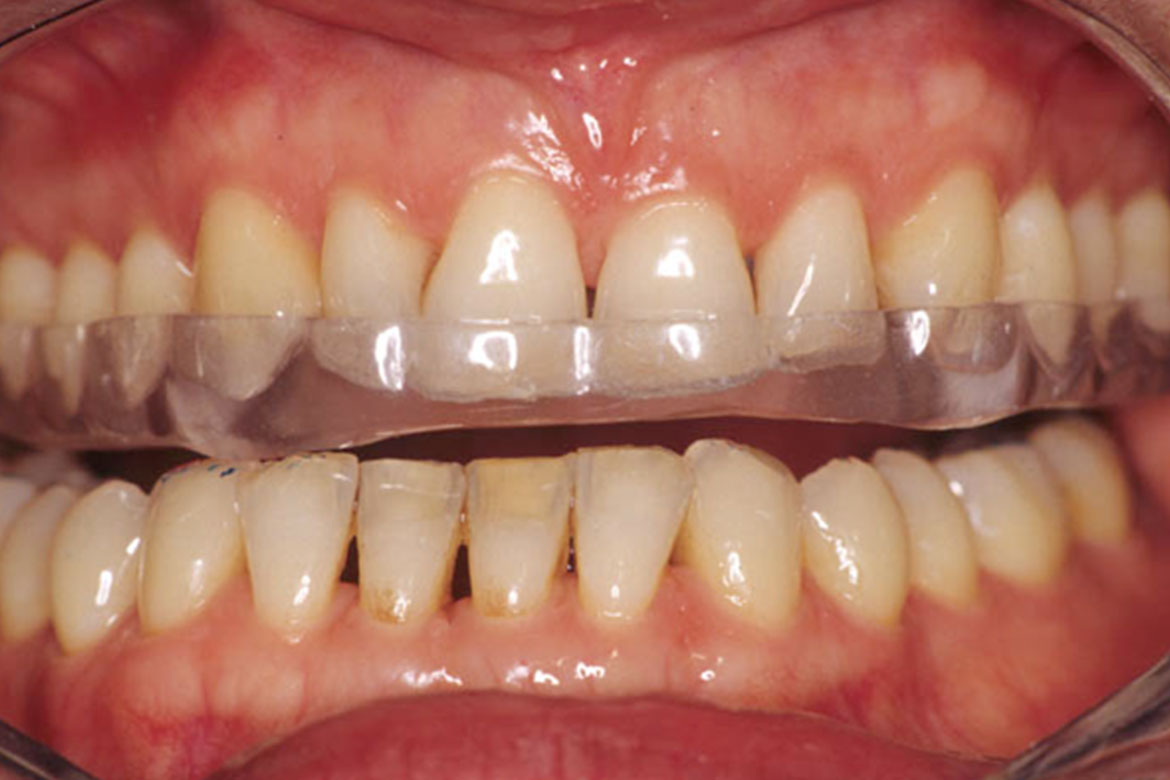

Sensibilité dentaire